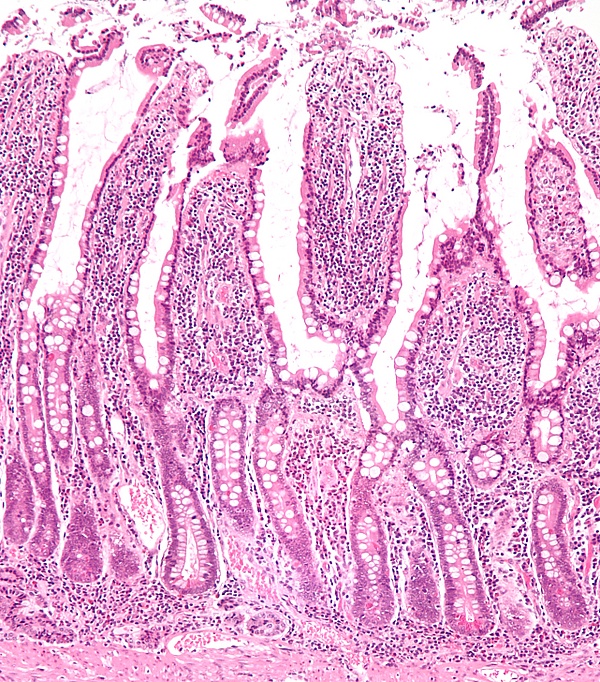

Слизистая оболочка тонкой кишки характеризуется характерным рельефом, образуемым наличием целого ряда анатомических образований: циркулярных складок, ворсинок и кишечных желез или крипт. Благодаря этим структурам увеличивается общая, в том числе и всасывающая поверхность, что способствует выполнению основных биологических функций тонким отделом кишечника[4]:

- кишечные ворсинки (лат. villi intestinales) образованы выпячиваниями слизистой оболочки пальцевидной либо листовидной формы, свободно выступающие в просвет тонкой кишки. Число ворсинок в тонкой кишке весьма значительно: наибольшее их количество в двенадцатиперстной и тощей кишках — насчитывается от 22 до 40 ворсинок на один квадратный миллиметр слизистой оболочки. Несколько меньше их в подвздошной кишке — от 18 до 31 ворсинки на один квадратный миллиметр;

- кишечные железы или крипты (лат. glandulae seu cryptae intestinales) представлены трубчатыми углублениями, расположенными в собственной пластинке слизистой оболочки, а их устья открываются в просвет тонкой кишки между кишечными ворсинками. При этом на один квадратный миллиметр поверхности слизистой оболочки тонкой кишки приходится до 100 крипт, общее их количество превышает 150 миллионов кишечных желёз на всём протяжении, а общая площадь крипт в тонкой кишке достигает 14 м2.

Стенка тонкой кишки образована серозным слоем, мышечным, состоящим из наружных продольных волокон и внутренних поперечных; и слизистой оболочки, соединяющейся посредством рыхлого подслизистого слоя с мышечным. Для слизистой оболочки тонкой кишки характерны особые поперечные складки (лат. valvulae conviventes Kerckringii), которых, однако, нет в верхней части двенадцатиперстной и в нижней части тонкой. Эти складки более часты в верхней части кишки, и каждая тянется приблизительно на половину окружности кишки. В нисходящей части двенадцатиперстной кишки имеется продольная складка на задней стенке. На нижней части этой складки на плоском сосочке открываются протоки поджелудочной железы и печени. Слизистая оболочка тонкой кишки имеет бархатистую поверхность, так как покрыта густо сидящими ворсинками (лат. villi intestinales). В стенке тонкой кишки залегают Либеркюновы железы (лат. glandulae Lieberkuehnianae), открывающиеся па́рами между ворсинками на всём протяжении тонкой кишки. В двенадцатиперстной кишке находится Бруннеровы железы, особенно многочисленные в её верхней части. По всей кишке разбросаны одиночные лимфатические узлы и скопления их — Пейеровы бляшки, наиболее многочисленные в нижнем отделе тонкой кишки. Внутри ворсинки находится сеть кровеносных капилляров и один или несколько лимфатических сосудов. Эпителий тонкой кишки цилиндрический и содержит бокаловидные клетки.